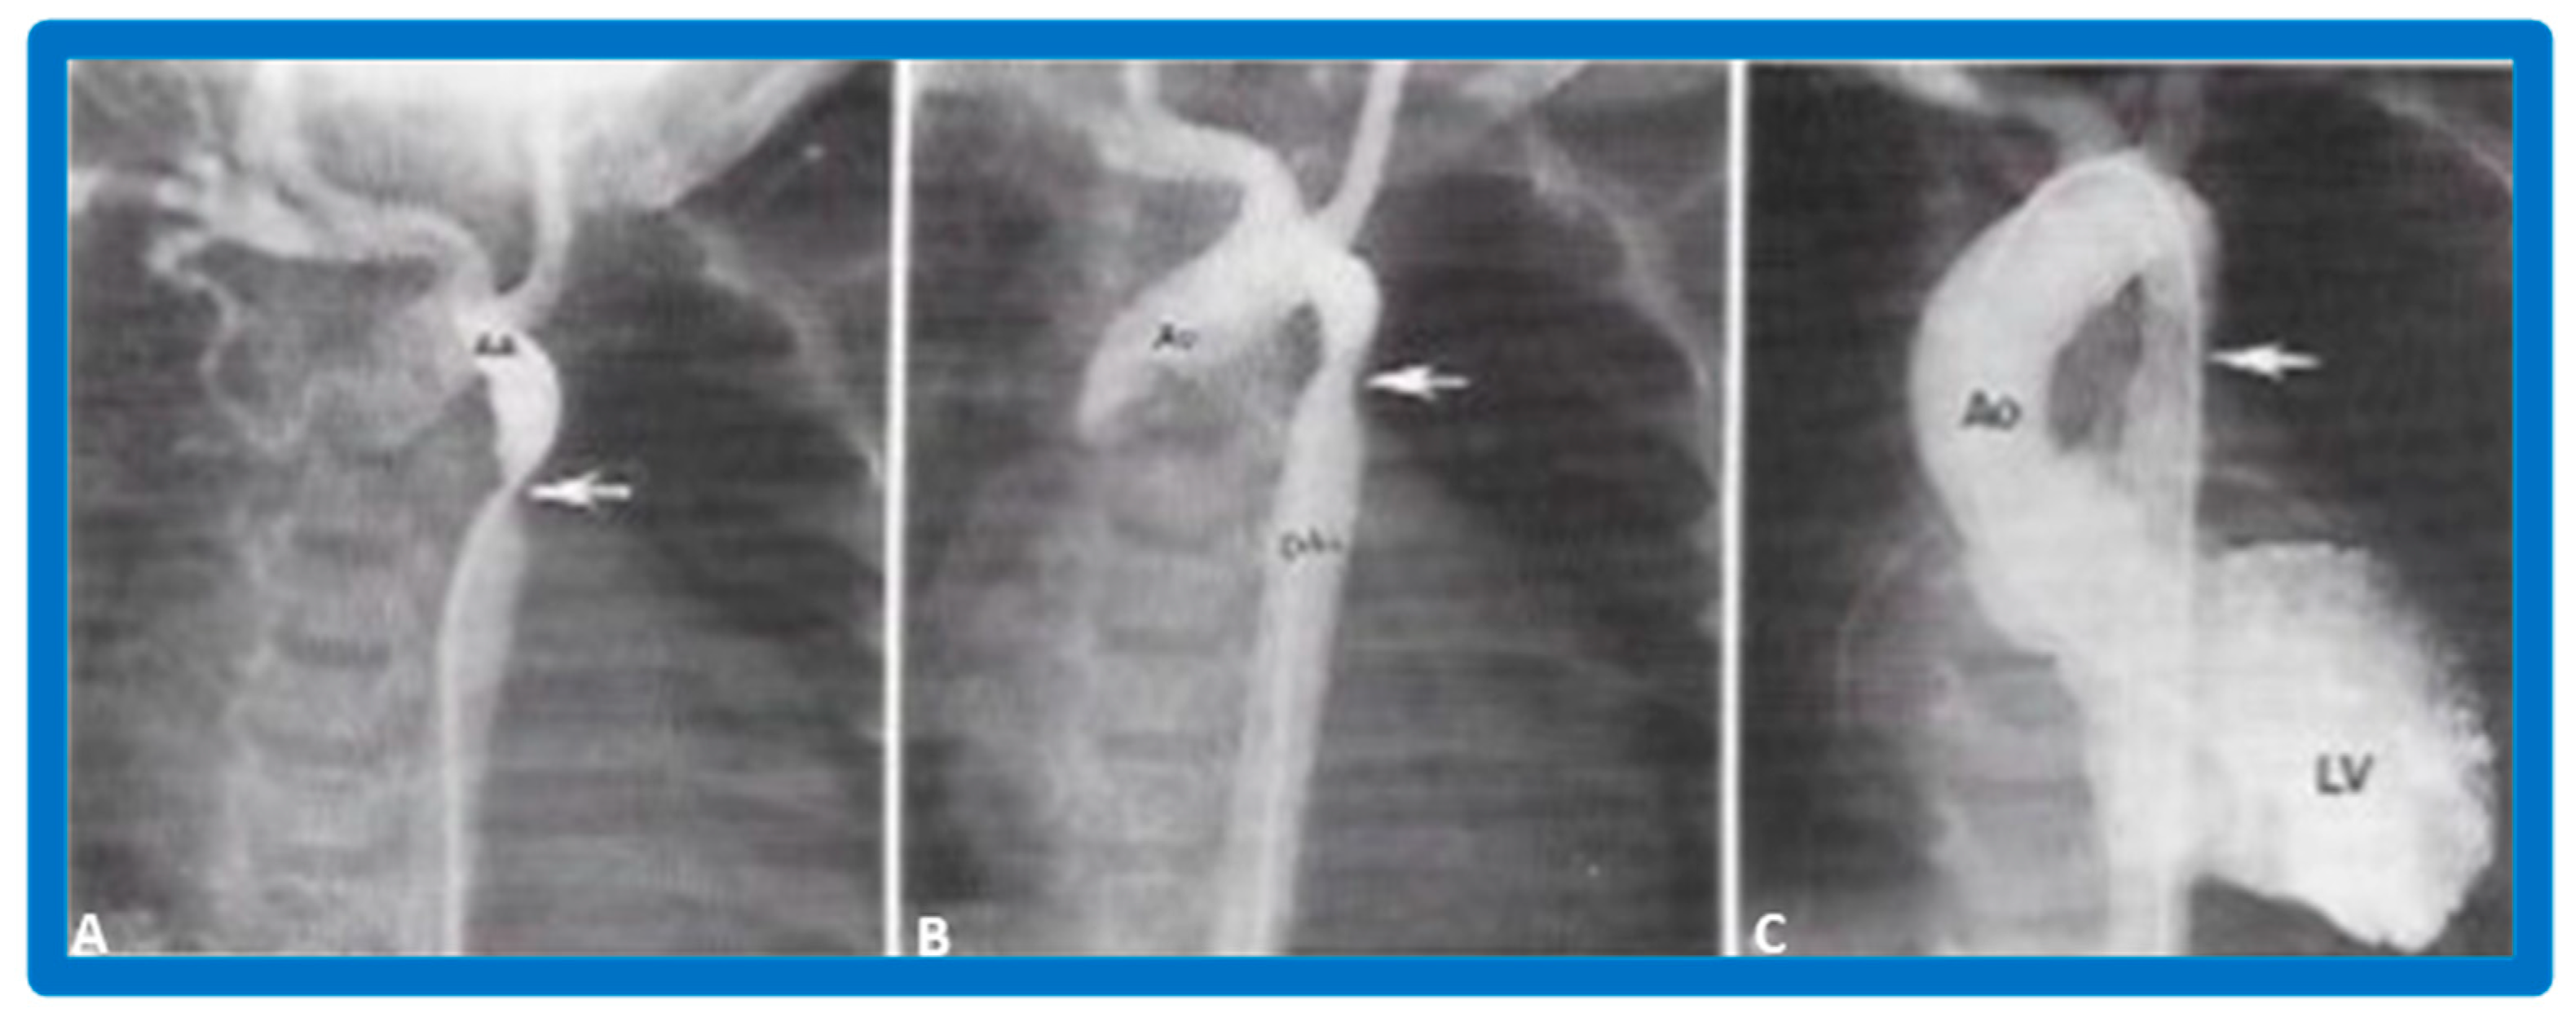

4.2. Aortic Stenosis

6.2.1. Residual Gradients